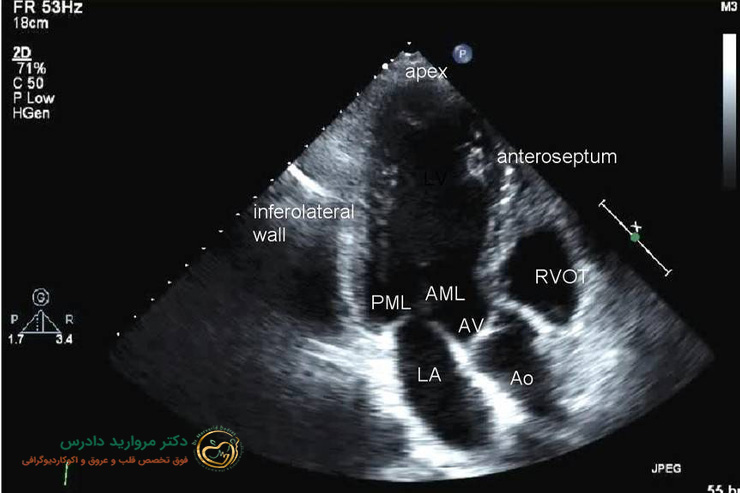

- اکوکاردیوگرافی (Echo) :

رایج ترین روش است که با استفاده از امواج صوتی، تصویر دقیقی از ساختار قلب ارائه می دهد و وجود سوراخ را نشان می دهد.